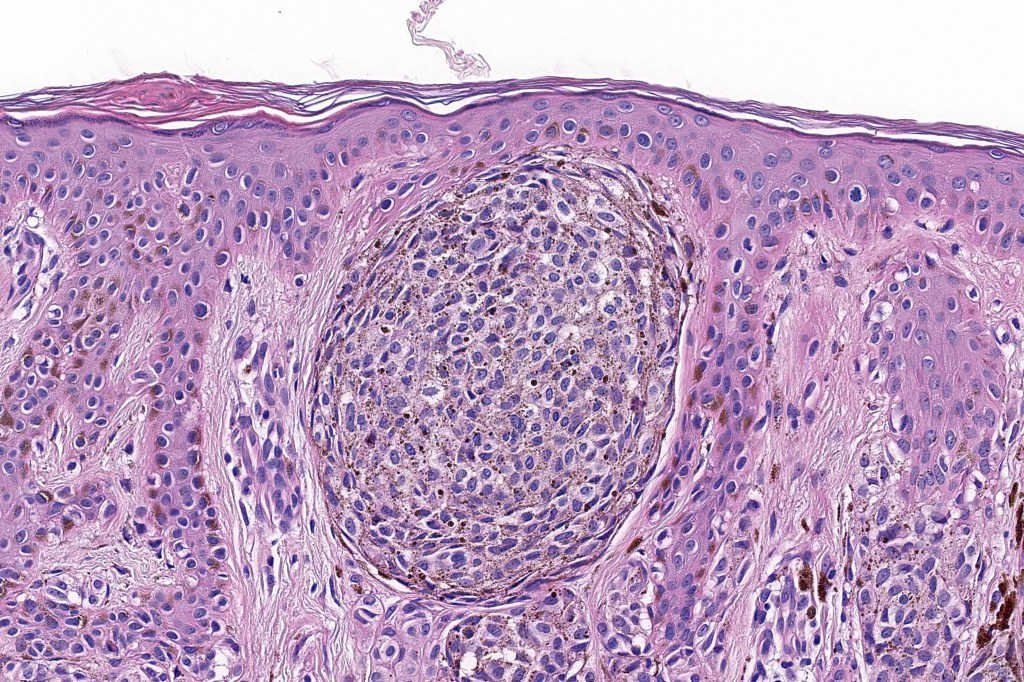

•Dermal of less often compound

•Wedge shape or less often plaque like silhouette

•Commonly associated with marked acanthosis/pseudoepitheliomatous hyperplasia although much less commonly, the epidermis is strteched over the lesion

•Composed of an admixture of large epithelioid melanocytes with vesicular nuclei containing a very prominent nucleolus (fried egg cells), spindle cells, dendritic cells & melanophages

•The epithelioid cells are typically very uniform